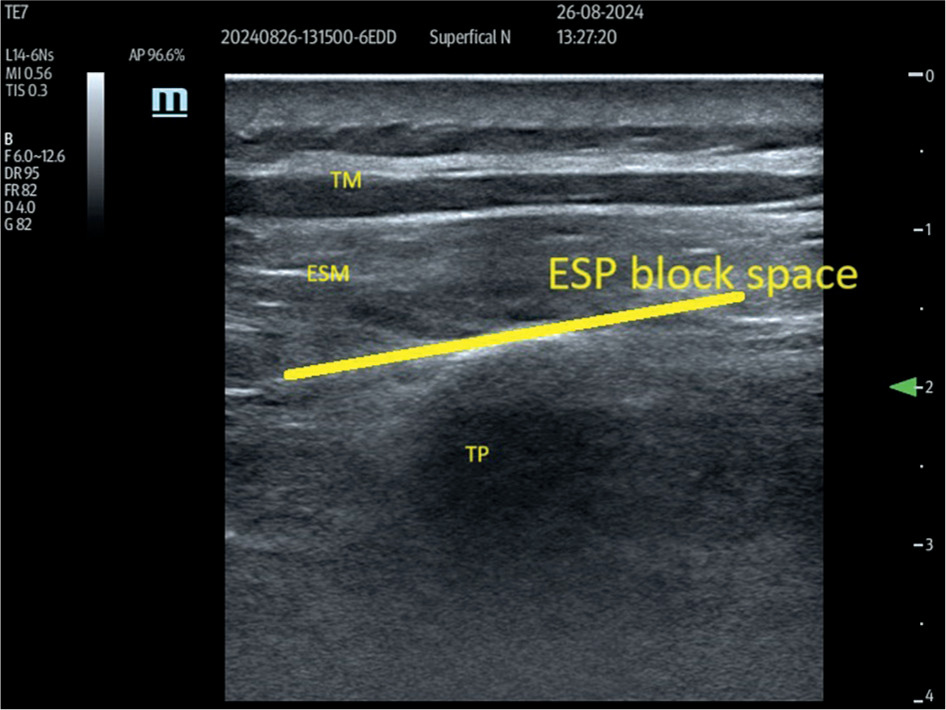

The ESP block was performed with the patient in a sitting position. After skin disinfection, a linear high-frequency (L14–6NS) ultrasound probe (Mindray, UMT-400, Mindray Building, Keji 12th Road South, High-Tech Industrial Park, Nanshan, Shenzhen, People’s Republic of China), covered with a sterile sheath, was positioned sagittally 1–2 cm lateral to the midline at the level of the ninth thoracic vertebra (T9). The T9 level was earlier identified by palpating the spinous process of the seventh cervical vertebra and counting down nine intervertebral spaces. After identifying the erector spinae muscle (ESM) and transverse process, a 21-gauge needle (Echoplex+ REF 6194.853 85 mm) was inserted deep into the ESM in a cranio-caudal direction, using an in-plane technique (Figure 1). The needle was advanced, ensuring that it crossed all muscle layers until it contacted the transverse process. Correct needle placement was confirmed by administering 0.5–1 mL of local anesthetic. After ensuring negative aspiration for blood, 30 ml of 0.35% ropivacaine was injected slowly deep into the ESM. This procedure was performed bilaterally on each patient.

FIGURE 1

Erector spinae plane (ESP) block block as seen on ultra-sound examination. Para sagittal ultrasound view at the T9 level in a slightly more medial plane prior to ESP block showing trapezius muscle and erector spinae muscle. The line shows the target site of the block. TM – trapezius muscle, ESM – erector spinae muscle, TP – transverse process